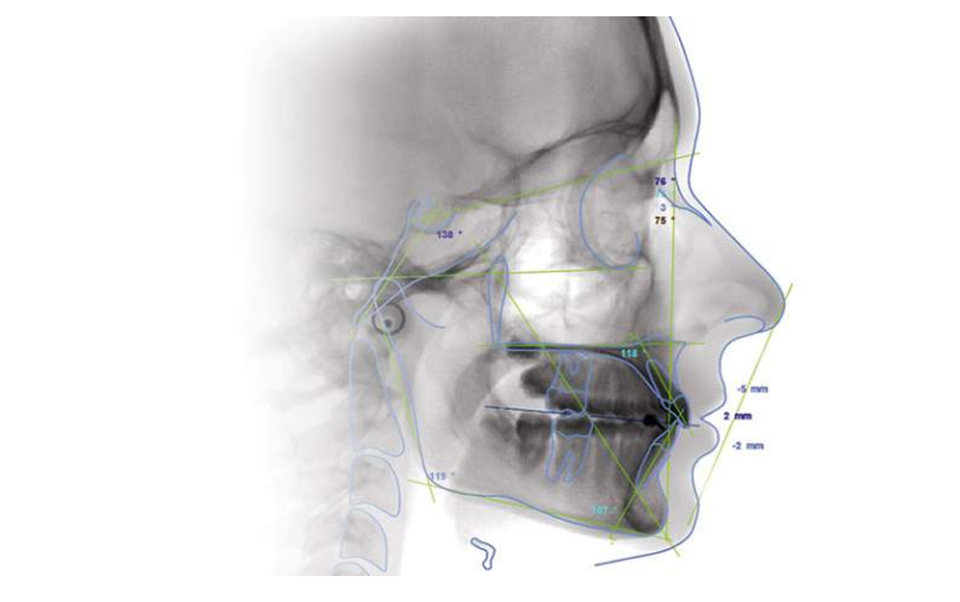

Radiografía de cráneo lateral o frontal. La más utilizada es la lateral en la que se aprecia con nitidez tanto el perfil blando (cara) como las estructuras óseas. Se puede practicar en posición postural, posición natural de la cabeza, etc. Utilizada principalmente en ortodoncia para estudios cefalométricos. También es de utilidad en estudios de posición cráneo-cérvico-mandibulares y en cirugía ortognática

Análisis dimensional realizado sobre una Telerradiografía, que permite determinar las relaciones de los diferentes componentes tanto duros como blandos de cara, maxilares y cráneo.